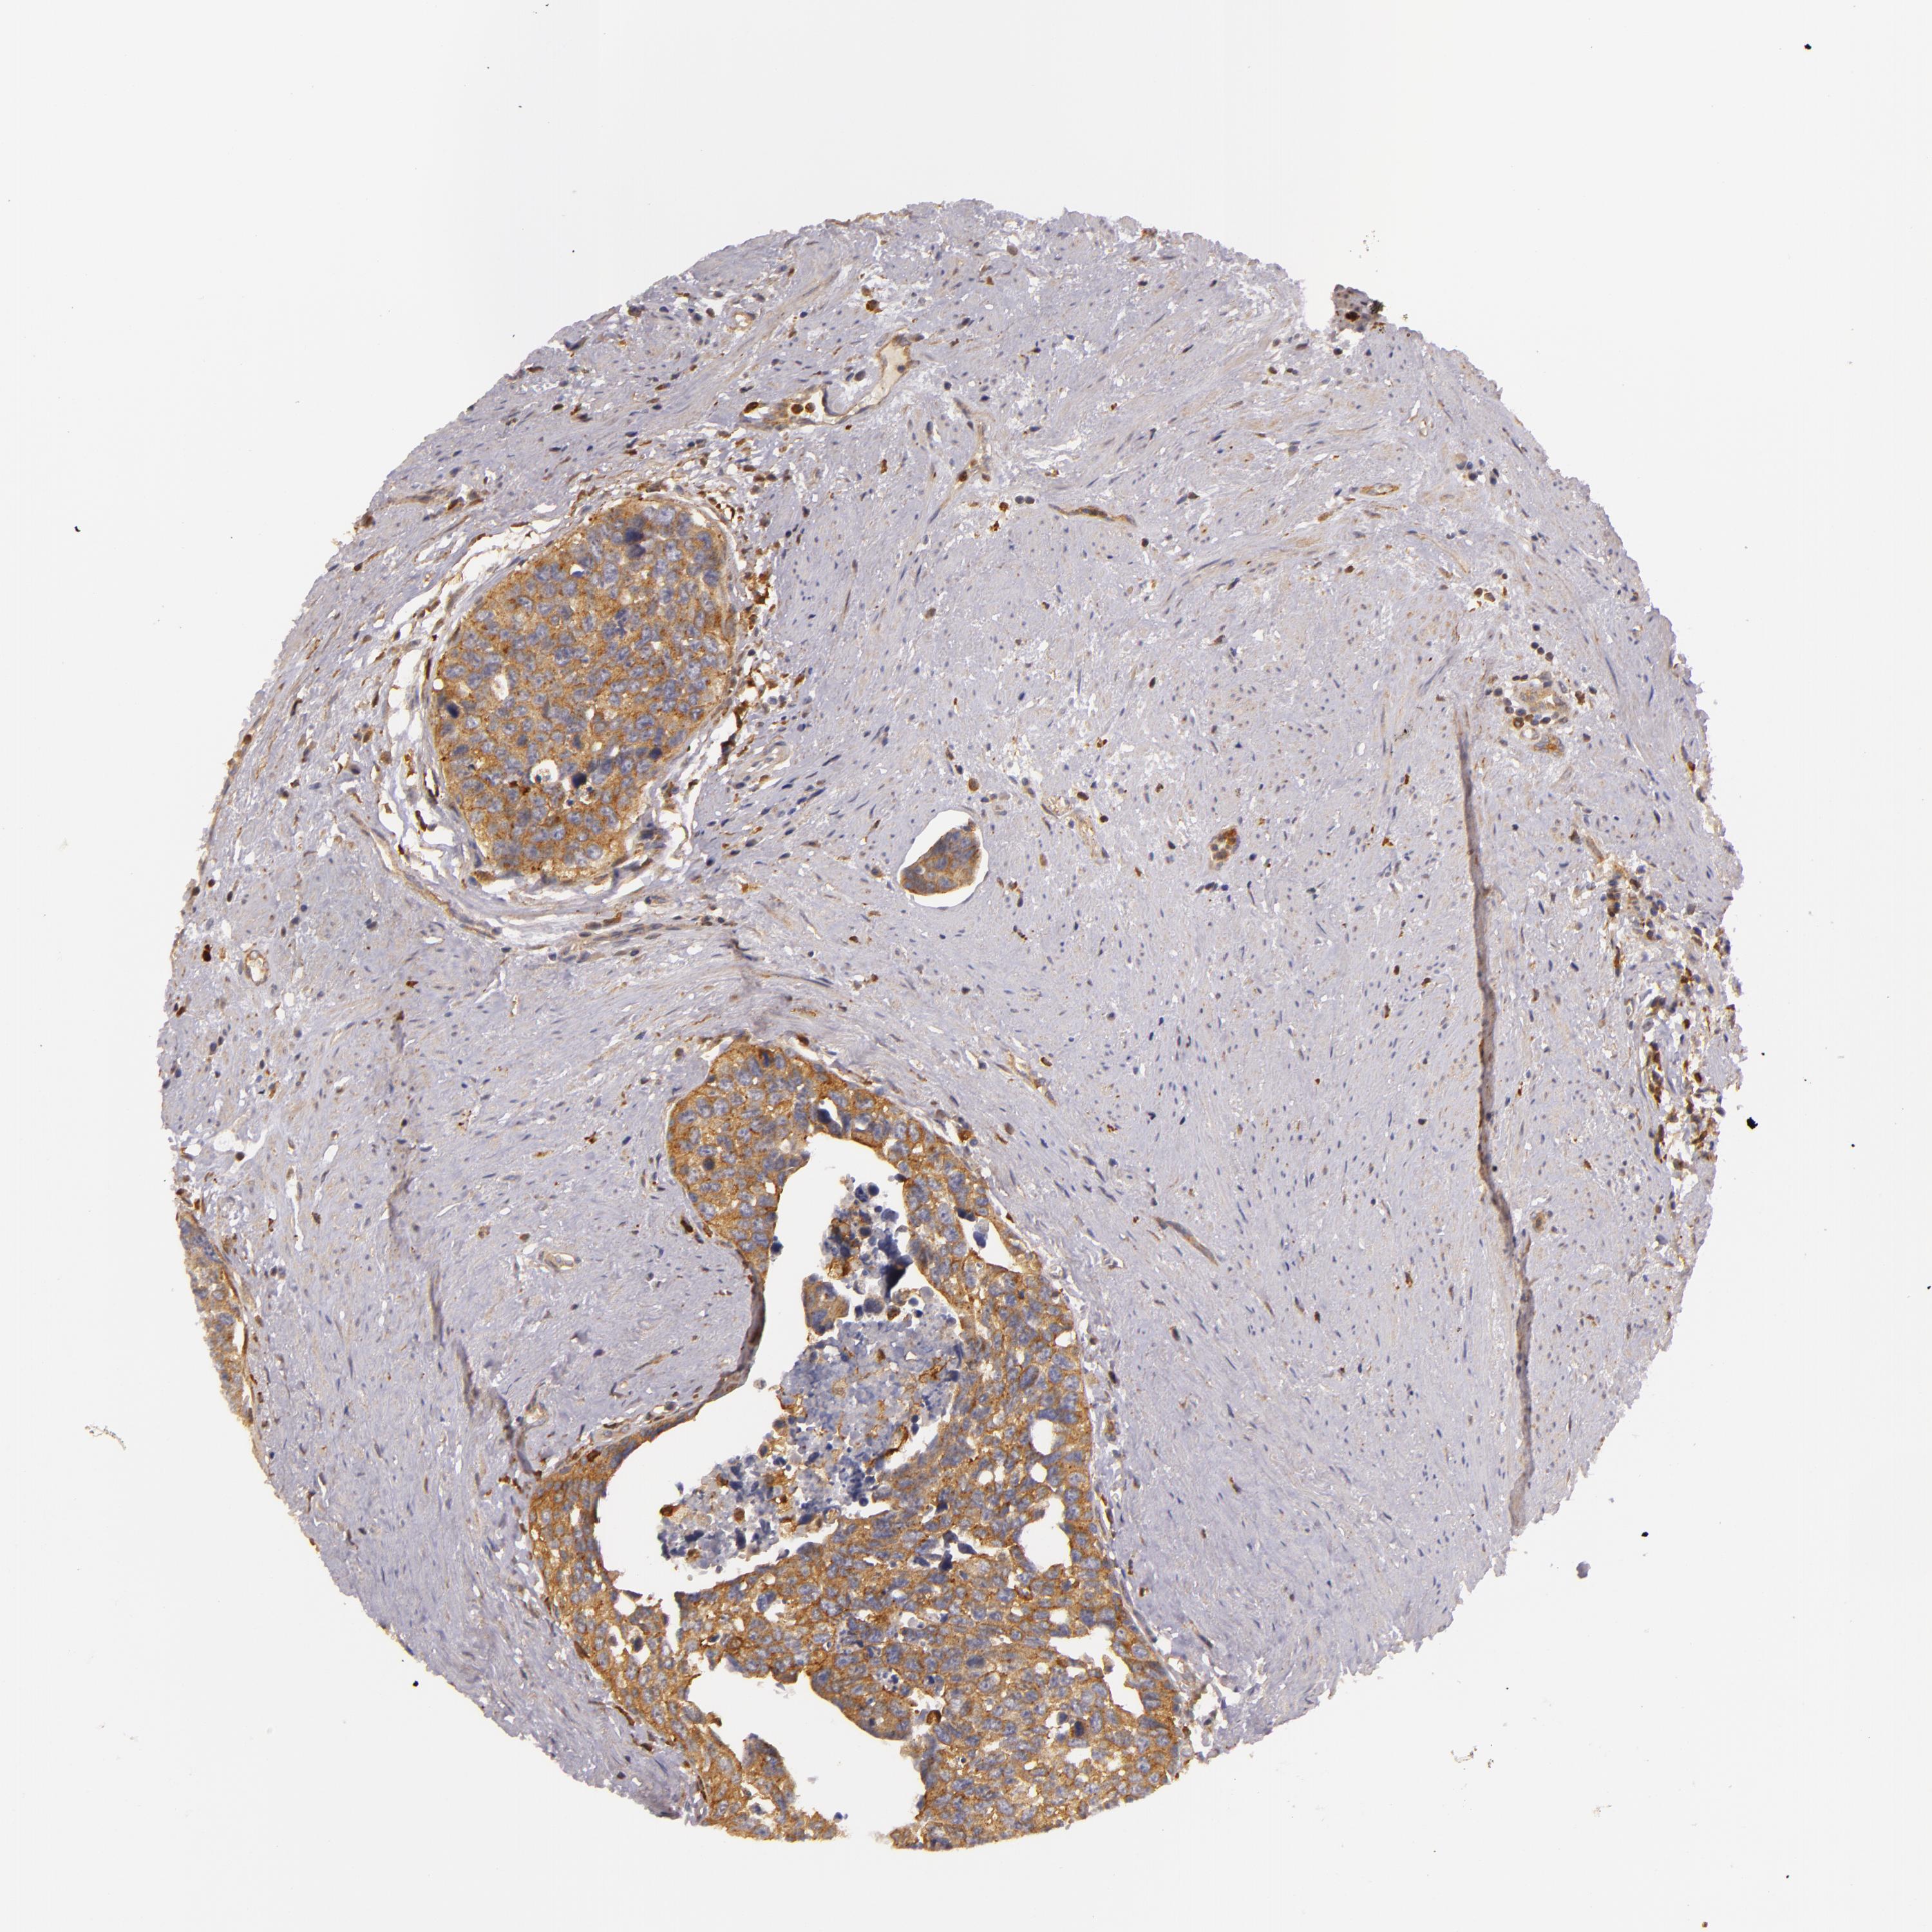

UROTHELIAL CANCER - Protein expressioni

A mouse-over function shows sample information and annotation data. Click on an image to view it in a full screen mode. Samples can be filtered based on level of antibody staining by selecting one or several of the following categories: high, medium, low and not detected. The assay and annotation is described here.

Note that samples used for immunohistochemistry by the Human Protein Atlas do not correspond to samples in the TCGA dataset.

Antibody stainingi

Antibody staining in the annotated cell types in the current human tissue is reported as not detected, low, medium, or high, based on conventional immunohistochemistry profiling in selected tissues. This score is based on the combination of the staining intensity and fraction of stained cells.

Each image is clickable and will lead to virtual microscopy that enables deeper exploration of all samples and also displays staining intensity scores, fraction scores and subcellular localization as well as patient and tissue information for each sample.

Antibody HPA001749

Staining

High

Medium

Low

Not detected

Intensity

Strong

Moderate

Weak

Negative

Quantity

>75%

75%-25%

<25%

None

Location

Nuclear

Cytoplasmic/membranous

Cytoplasmic/membranous,nuclear

Urothelial carcinoma, High grade